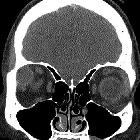

CT

Axial and coronal CT shows peripheral and mild central heterogeneous enhancement.